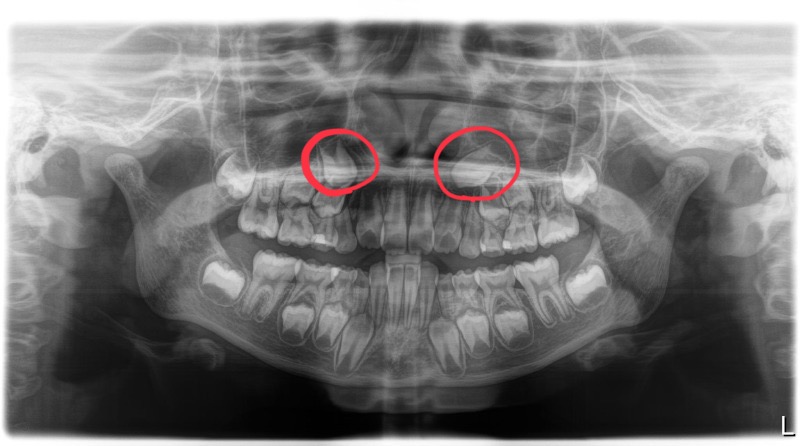

レントゲンでの現状

検査時のレントゲンです。

赤い丸で囲っているのが3番目に生えてくる歯ですがかなり角度が斜めになっています。

この角度が強いと最悪の場合出てこないで埋まったままになってしまいます。